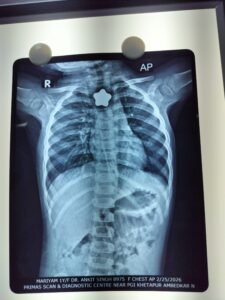

एक्स-रे जांच में भोजन नली में चुंबक फंसा हुआ पाया गया। स्थिति की गंभीरता को देखते हुए चिकित्सकों ने बिना विलंब ऑपरेशन की तैयारी की।